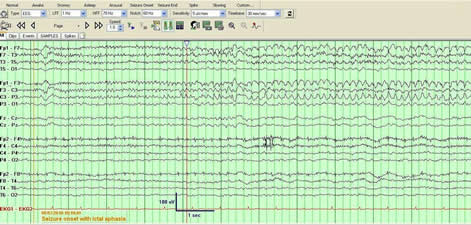

Rationale: Lacosamide is a novel AED approved for the treatment of partial epilepsy. Anecdotal reports have suggested efficacy in patients with status epilepticus or acute repetitive seizures though such cases are relatively few in the published literature.Methods: We report three patients who presented with either acute repetitive seizures or with NCSE who were refractory to conventional therapy but responded rapidly to intravenous lacosamide. Continuous video-EEG monitoring data was reviewed and correlated with the response to lacosamide.Results: A 60 year old man with left frontotemporal anaplastic astrocytoma was admitted for ictal aphasia refractory to appropriate doses of valproate, pregabalin and levetiracetam. EEG showed almost continuous left hemispheric electrographic seizures (Figure 1). After receiving 100 mg of intravenous lacosamide and initiation of maintenance therapy there was resolution of aphasia and the ictal pattern over a 24 hour period. A 56 yr old man with left intraparenchymal and subarachnoid hemorrhage developed worsening confusion followed by a GTC seizure. He was noted to have continuous electrographic seizures emanating from the left hemisphere and were associated with persistent confusion and orofacial automatisms. After failing to improve with adequate doses of phenytoin, 300 mg intravenous lacosamide was given as a load followed by 100 mg twice daily. Within twelve hours by EEG criteria his seizure frequency declined to < 75% and by 24 hours resolved completely. A 84 year old man with history of right hemispheric stroke and mild cognitive impairment was admitted for confusional episodes. He was noted to have electrographic seizures originating from either hemispheres associated with staring and dysphasia. After failing to respond to appropriate doses of intravenous Levetiracetam, to avoid sedation intravenous Lacosamide was introduced at 100 mg twice daily that resulted in rapid reduction of seizure frequency and eventually complete resolution of seizures within 36 hours. Subsequent inadvertent discontinuation of lacosamide as an outpatient resulted in recurrence of seizures, however, reintroduction of Lacosamide resulted in excellent seizure control. Conclusions: Based on our results, in patients with refractory acute repetitive seizures or non-convulsive status epilepticus lacosamide appears to be a very effective and safe alternative. Further studies are needed to elucidate the role of lacosamide as an adjunctive medication in patients with status epilepticus.